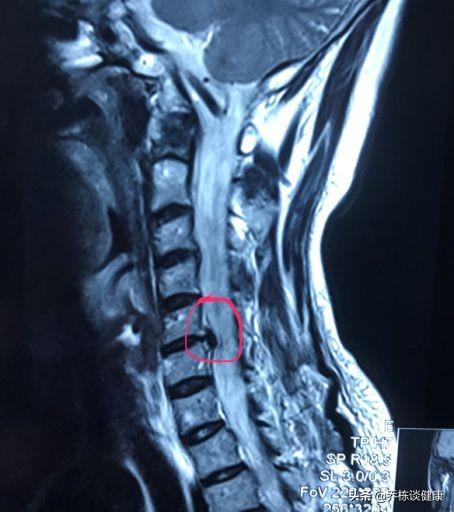

頚椎症の診断には、MRIなどの頚椎病変の画像変化があり、同時にそれに対応する臨床症状が伴っていなければならず、どちらか一方が欠けても診断がつかない。一つの項目だけで診断を下すことはできない。

頚椎症の中でも、脊髄頚椎症と呼ばれる攻撃的なタイプの頚椎症があり、これは椎間板ヘルニアが脊髄を直接後方に圧迫し、脊椎の変性をもたらすためです。MRI検査で中心型の頚椎椎間板ヘルニアが検出され、ヘルニアがより深刻な場合は、頚椎を保護するために、急ブレーキや急発進、頚部に大きな衝撃を与えないように、また、麻痺を引き起こすむち打ちの動きを見せないように、特別な注意を払う必要があり、これは非常に深刻な結果をもたらす可能性があります。